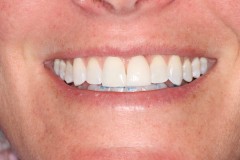

This young patient was self-conscious about the appearance of her short teeth and gummy smile. Through crown lengthening and tooth whitening procedures, we were able to create a beautiful, more mature smile.